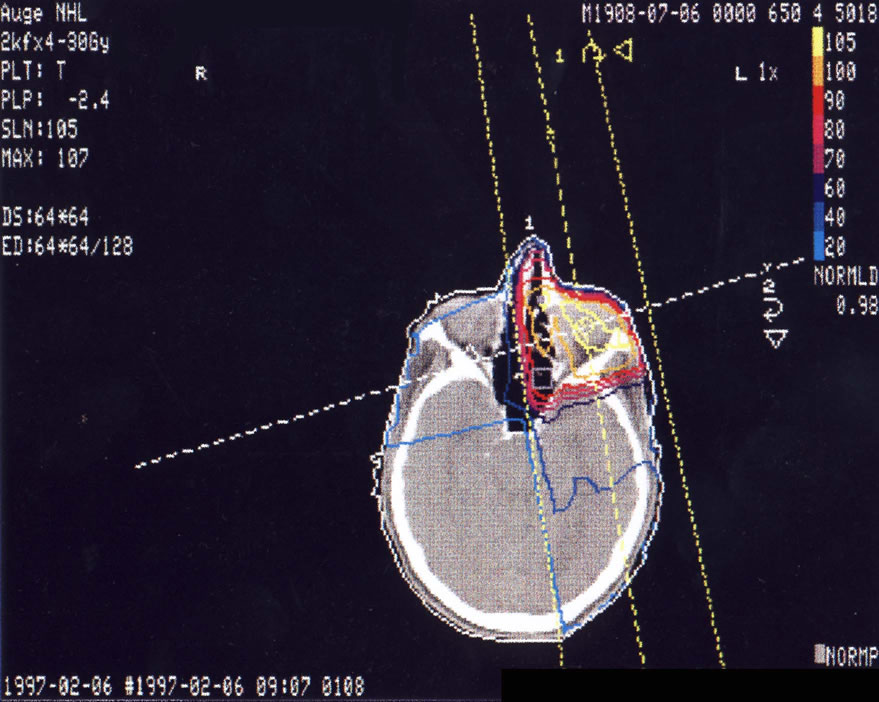

Tumore im Bereich des Auges

Einführung aktuelle Bilder - Einführung Bestrahlungspläne - Einführung Demonstration